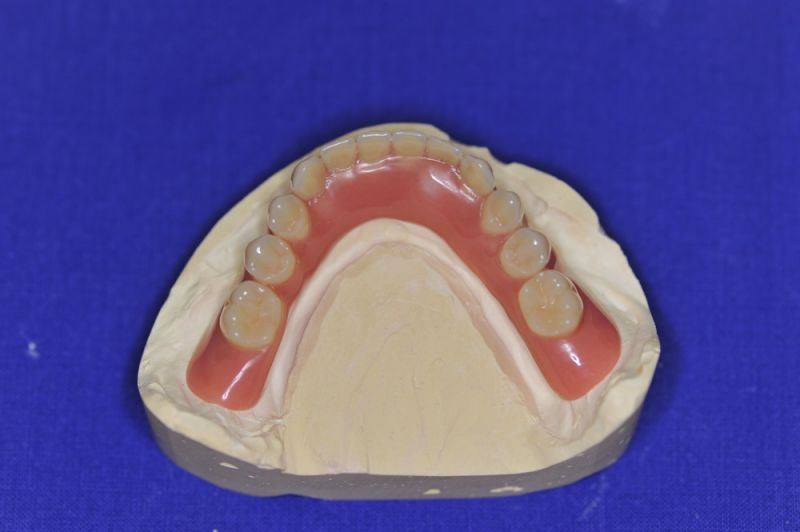

Patient aus der Region Eckernförde erhält neue implantatgestützte Cover Denture Prothesen

Der Patient erhält heute eine neue implantatgetragene Prothesenrekonstruktion im Ober- und Unterkiefer.

Die Neuversorgung war weniger einem ausgewechselten Implantat geschuldet, als der Langjährigkeit der bestehenden Arbeit und der damit verbundenen Materialermüdung.

Die Arbeit wurde im Jahr 2005 inkorporiert, war damit also 10 Jahre in Funktion und wurde mehrfach umfangreich überarbeitet und instandgehalten.